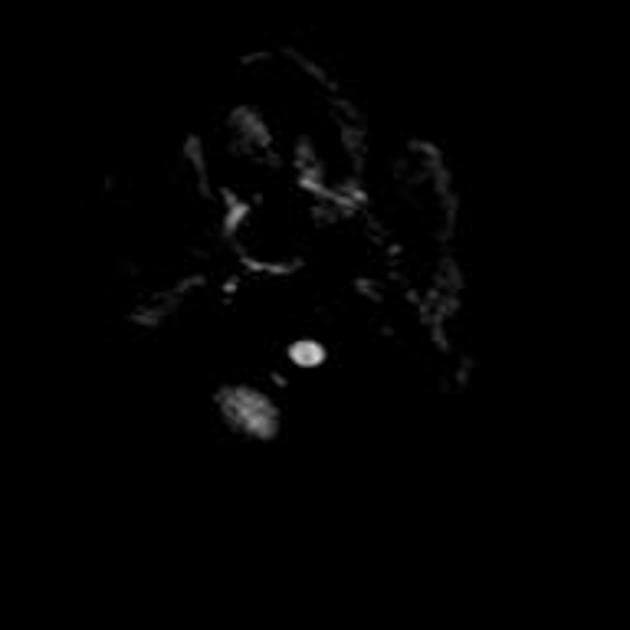

Axial ADC

- Có một phần hạn chế khuếch tán (diffusion restriction) ở vùng ngoại vi, nhưng không có ở trung tâm.